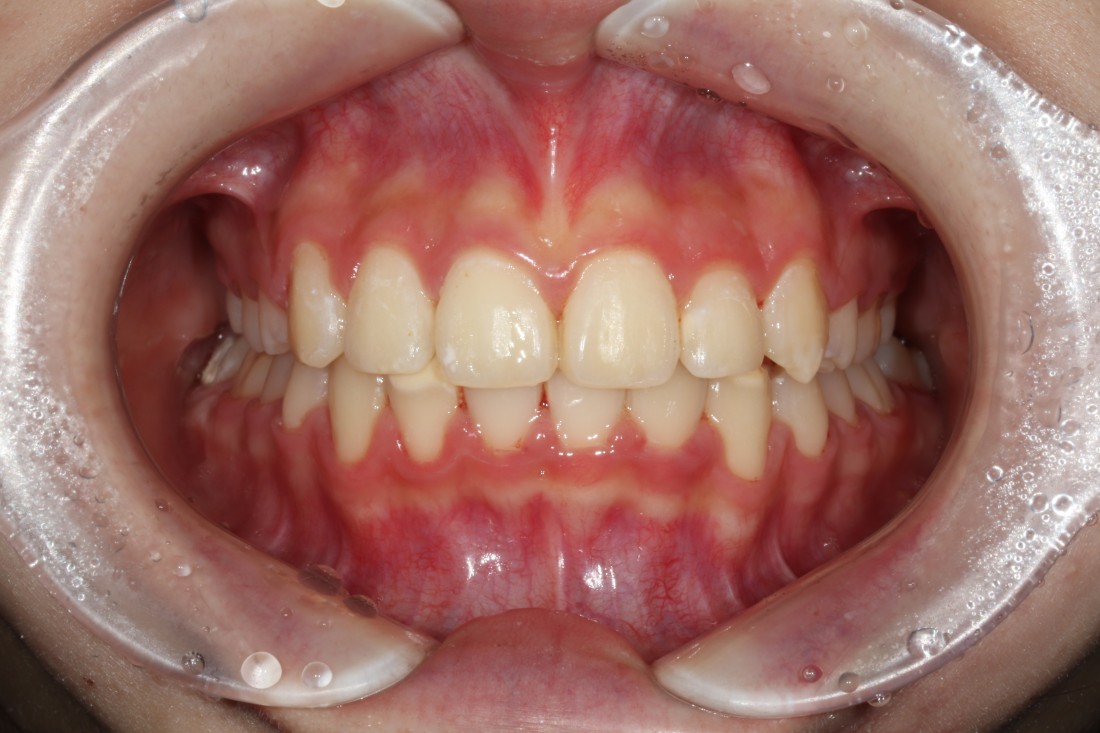

때로는 치아교정만으로 해결하는 것 보다

임플란트 식립을 동시에 해서

더욱 최상의 치료결과를 얻을 수 있을 때가

생기는데요.

20년 경력의 교정전문의 진료와 함께

구강외과 전문의 대표원장님의

협진도 동시에 진행하여

치아교정 기간을 단축하고

성공적으로 고른 치열을 완성하였습니다.